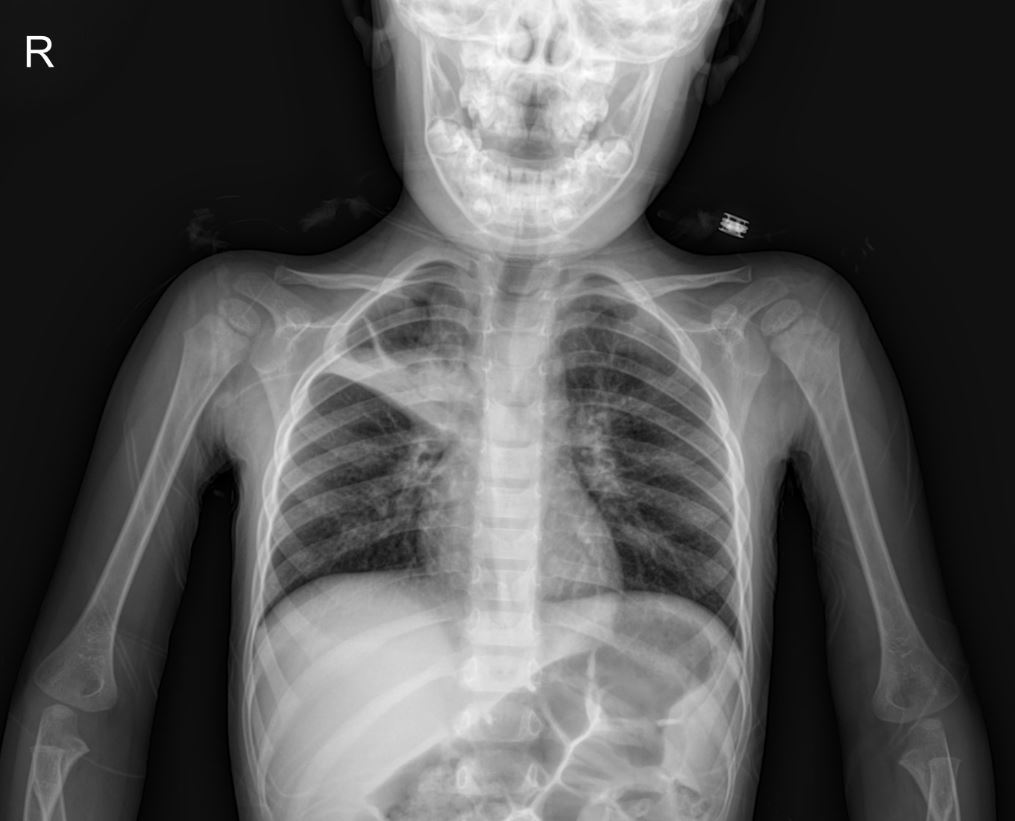

A posteroanterior (PA) chest X-ray was performed upon admission.

- X-ray Interpretation: The PA chest X-ray revealed a linear fissure area in the right upper zone. This finding raised suspicion for pneumonia, particularly given the diminished breath sounds in that area during physical examination.

The patient was admitted with preliminary diagnoses of possible lung fissure (pneumonia) and for monitoring of hyperglycemia.

This case highlights the importance of thorough clinical and radiological assessment in pediatric patients presenting with respiratory symptoms. The presence of a linear fissure on chest X-ray in a child with a barking cough and diminished breath sounds warrants consideration of pneumonia, even in the context of typical croup symptoms. Furthermore, the incidental finding of significant hyperglycemia underscores the need for comprehensive initial workups and vigilance for unexpected systemic conditions, such as new-onset diabetes.